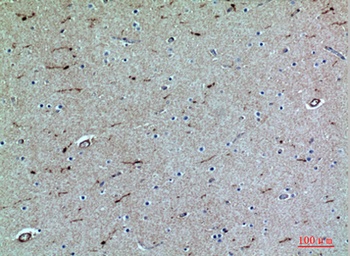

Formalin-fixed, paraffin-embedded human Spleen stained withCD162 Monoclonal Antibody (PSGL1/1601).